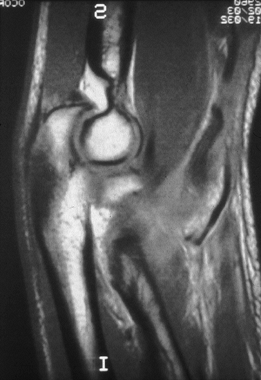

Unfortunately, the magnetic resonance imaging (MRI) scan is not always

capable of delineating the difference between degenerative tendinitis

that is otherwise asymptomatic, and symptomatic tendinitis or a tear

with associated laxity. An MRI scan revealing a normal ulnar collateral

ligament (Fig. 81.7) can provide impetus to search for a different diagnosis. Arthrography is not useful

because of frequent false negative findings in cases of chronic ulnar collateral ligament insufficiency with an intact capsule.